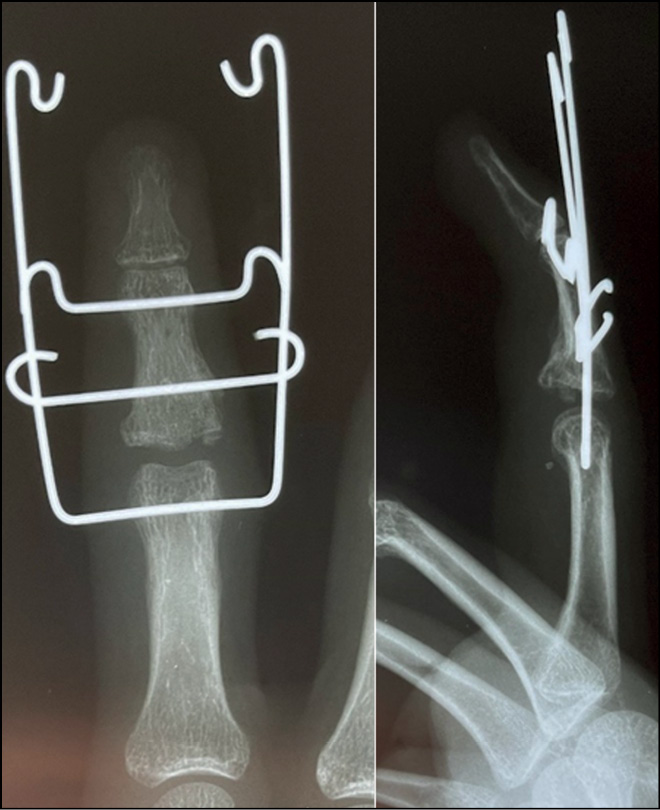

Method of treatment of patients with damage to the dorsal edge of the base of the middle phalanx accompanied by failure of the central bundle of the tendon of the common extensor tendon of the triphalangeal fingers of the hand

In the preoperative period, a computed tomographic study of the patient’s injured hand and contralateral foot is performed. Spatial visualization of the injured middle phalanx and middle phalanx of the second toe is performed. A solid polyacrylate template is created, corresponding to the dimensions of the future resection of the area of the damaged base of the middle phalanx, comparable with the dimensions of the future bone autograft from the dorsal edge of the base of the middle phalanx of the second toe.

In the supine position, the hand was placed on an extension table, and a pneumatic cuff was applied. An arc-shaped incision was made along the dorsal surface in the projection of the PIP joint of the injured finger of the hand, involving the removal of a skin flap. Blunt and sharp access to the extensor tendon and joint capsule was achieved. The lateral legs of the extensor tendon were isolated and withdrawn. The joint capsule was dissected transversely. Dislocation of the PIP joint to the rear was performed, and scar tissue was excised. The damaged area to the articular surface of the dorsal edge of the base of the middle phalanx was identified, and a sparing resection of the damaged portion of the phalanx was performed using a pre-created 3D template. A pre-created individual polyacrylate template was attached to visualize the necessary parameters of the future graft from the middle phalanx of the second toe of the left foot. A separate linear skin incision was made along the dorsal surface of the PIP joint area of the II toe of the contralateral foot. The central bundle of the tendon of the long extensor tendon of the toe was isolated. The phalanx was marked according to the dimensions of the middle phalanx defect using a 3D template. An osteotomy of the outlined section of the middle phalanx of the second finger was performed using an oscillatory saw. Using a chisel, a fragment was isolated from the wound, cutting off the central bundle of the long extensor tendon 4 cm from the attachment site. The graft was fixed to the phalanx with a bone holder and alternately drilled in the palmar direction. Two 1.5 mm screws were inserted to fix the graft with the palmar edge of the middle phalanx. The phalanx dislocation was corrected. EOT control was performed, and the position of the phalanges and screws was correct. Arthrodesis of the PIP joint of the second toe with spokes was performed. A layer-by-layer suture of the wound of the II toe of the left foot and rubber drainage were performed. The suture of the tendon end of the graft with the central bundle of the common extensor bundle of the wrist finger was performed using U-shaped sutures, along with adaptation sutures of the tendon edges. The skin flap was sutured with knotted sutures. An aseptic dressing was applied. Fixation in a palm plaster bandage in the position of flexion in the PIP joint was at 30°.

There is a patent application for invention No. 2022133417, “Method of surgical treatment of malpositioned fracture dislocations of the dorsal edge of the base of the middle phalanx of the triphalangeal fingers of the hand using an autograft from the middle phalanx of the second toe of the patient’s contralateral foot,” dated 20.12.2022 (Figs. 14−23).

Fig. 21. X-ray control after osteosynthesis of the graft and arthrodesis of the proximal interphalangeal joint of the toe.

Fig. 22. X-ray control 2 months after the operation.